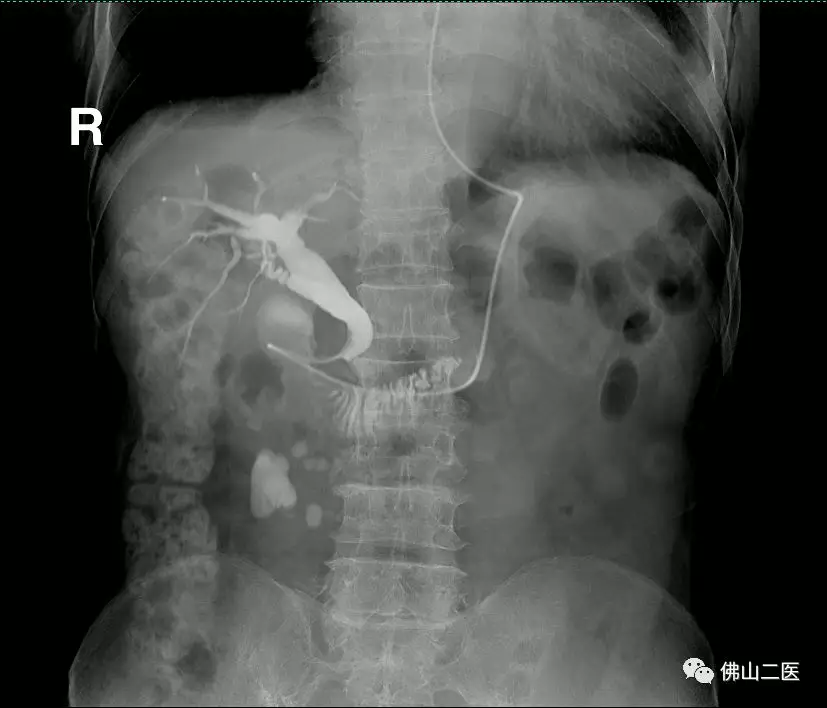

X光监视下看到白色箭头所示胆管内造影剂缺损图形判断为结石占位影像

取出解释后结石后,球囊堵住胆管末端实施全胆管系统造影,明确无结石残留情况

术后第二天再次造影明确胆管内无残留结石并胆道通畅